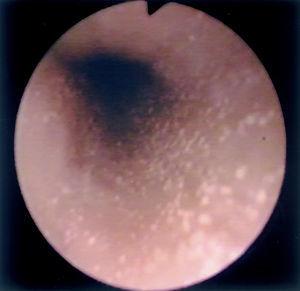

Al estudio endoscópico, en 2 pacientes (18,18 %) se observó una pérdida del patrón circular normal y tendencia a la traquealización (aspecto corrugado y patrón triangular con escasa insuflación) (fig. 1). En otros 2 pacientes se observaron lesiones puntiformes de aspecto blanquecino que correspondieron a acumulaciones de eosinófilos en el estudio histológico (figs. 2 y 3) y en un paciente se observó discreto prolapso cardial. En los otros 6 pacientes los resultados macroscópicos eran normales.

Figura 2. Punteado blanquecino visible en el estudio endoscópico en uno de nuestros pacientes afectados de esofagitis eosinofílica.

En cuanto a los hallazgos endoscópicos pueden ir desde un aspecto de la mucosa esofágica estrictamente normal a diferentes patrones de alteración endoscópica. Se ha descrito la existencia de imágenes erosivas longitudinales, granularidad, pérdida del patrón vascular, estenosis focales6, estenosis de larga extensión ("esófago de pequeño calibre")17 y fragilidad mucosa de fácil erosión al contacto con el endoscopio (denominado como crêpe paper esophagus)18. Pero el patrón que se ha comunicado con más frecuencia es el de traquealización esofágica, denominado de este modo por la presencia de imágenes de anillos transversales consecutivos que recuerdan el aspecto "corrugado" de la tráquea y que corresponderían a contracciones intermitentes de la musculatura circular esofágica19. Otra imagen bastante característica en estos pacientes es un punteado blanquecino que semeja el aspecto de candidiasis esofágica y que corresponde a acumulaciones o microabscesos constituidos por eosinófilos que protruyen sobre la superficie mucosa, como se demuestra por el estudio anatomopatológico20,21. En dos de nuestros pacientes se demostró este hallazgo.